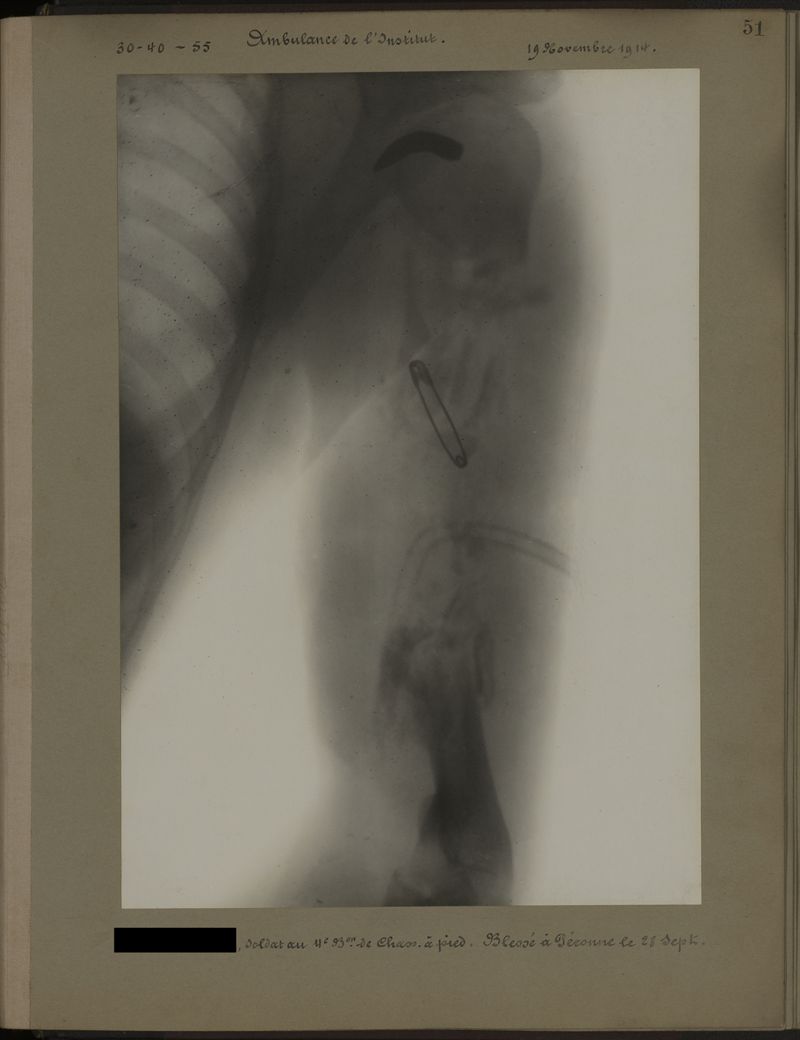

Deux albums de radiographies de la Première Guerre mondiale. Collection du laboratoire central de radiographie de la Salpêtrière. Deuxième album.

1915.